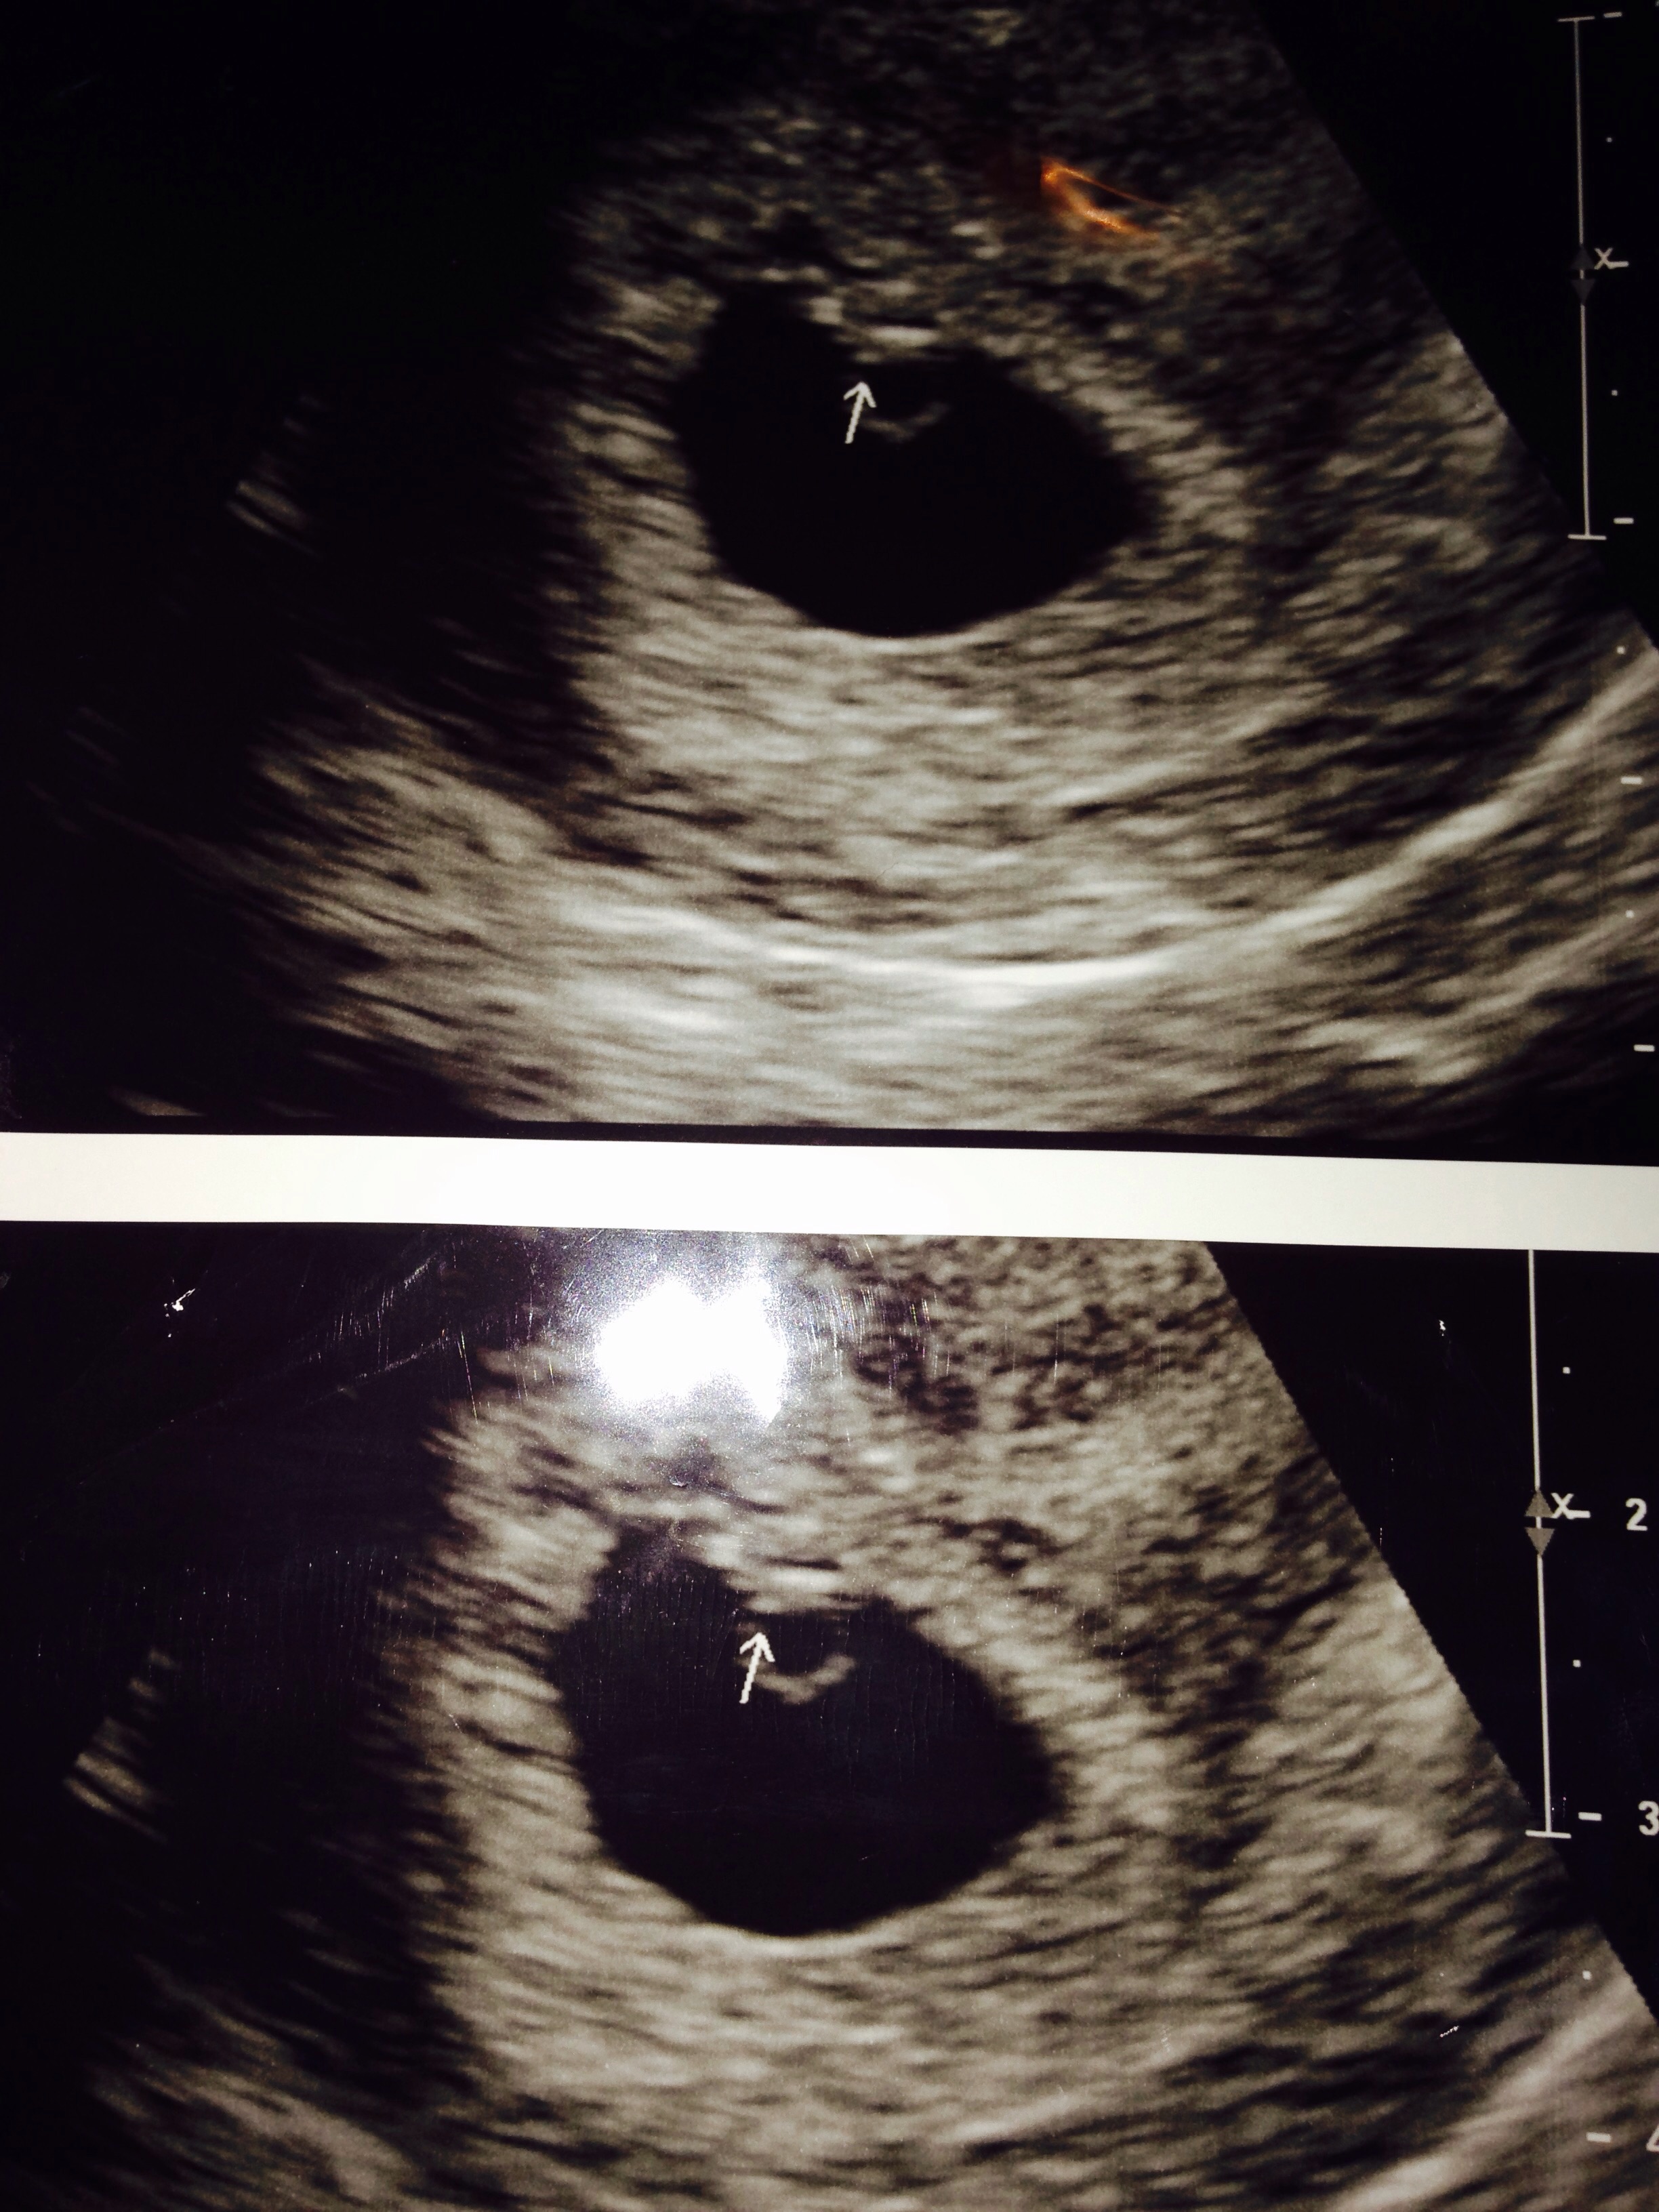

New discussion button is missing for me on my laptop. I had my first appt today expecting to be 8 weeks based on LMP. They did a transvaginal ultrasound because they were worried about a possible cyst and the sac was measuring at only 5w4d. You couldn't see anything in it yet. Based on when I think I ovulated, this would make sense... my cycles are usually long... but that didn't stop me from bursting into tears. Neither the tech or the doctor were worried and they want me to come back in 2 weeks for another ultrasound, but I'm freaking out. Is 5w4d just too early to see anything? Did anyone else have their EDD completely wrong when they went for an ultrasound?

If your cycles are unusually long, you shouldn't have based how far along you thought you'd be on your LMP. So, if you are only 5w4d, seeing the gestational sac sounds fine. I only saw the gestational sac at 5w2d, saw the yolk sac four days after that and saw the heartbeat at my 7w appointment. I know it's really hard (especially when so many other women see things a lot earlier), but try to remain calm and think positively.